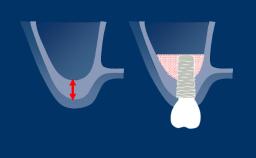

O sucesso do tratamento com implantes requer um plano com orientação protética para determinar a posição ideal do implante. A posição do implante deve facilitar a instalação de uma prótese definitiva ideal que atenda às exigências funcionais e estéticas e mimetize a dentição natural.

Usando investigações diagnósticas adicionais, os requisitos cirúrgicos e protéticos específicos da região podem ser identificados e avaliados. Isso ajuda a minimizar o risco de complicações e falhas após o tratamento com implantes.